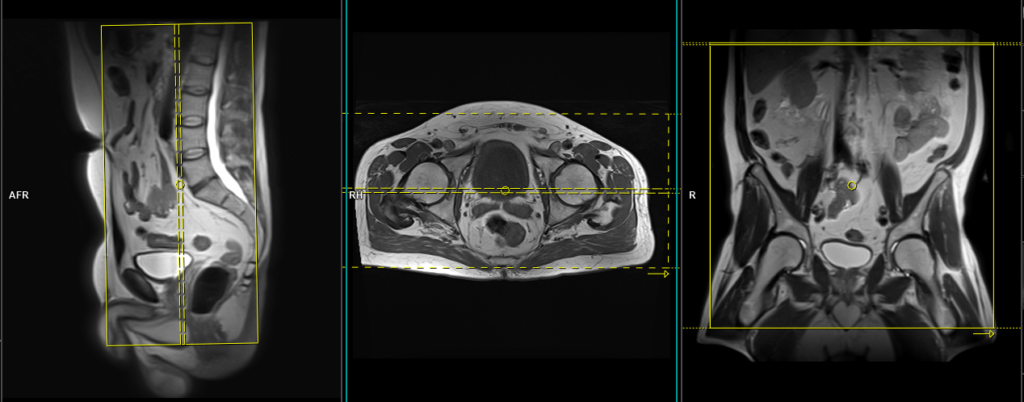

T2 stir coronal 5 mm Large FOV

Plan the big FOV coronal slices on the sagittal plane; angle the position block parallel to the lumbar spine. Check the positioning block in the other two planes. An appropriate angle must be given in the axial plane (parallel to the line from right to left hip joint). Slices must be sufficient to cover the para aortic area from mid abdomen to the sacrum. FOV must be big enough to cover the abdoman and pelvis (normally 380mm-400mm). Big FOV scans are normally taken to check the Para-aortic and pre-sacral nodes.

Parameters

TR 4000-5000 | TE 110 | FLIP 130 | NEX 2 | SLICE 5MM | MATRIX 384X384 | FOV 380-400 | PHASE R>L | GAP 10% | TI 150 |

T1 tse axial 6 mm Large FOV

Plan the large FOV coronal slices on the sagittal plane, angling the positioning block vertically across the abdomen and pelvis. Verify the positioning block in the other two planes. Ensure an appropriate angle is given in the axial plane (parallel to the line from the right to the left hip joint). The slices must sufficiently cover the abdomen and pelvis from the anterior abdominal wall to the sacrum. The FOV should be big enough to encompass the abdomen and pelvis (normally ranging from 380mm to 400mm). Large FOV scans are commonly performed to assess the local spread of diseases and to evaluate the para-aortic and pre-sacral nodes.

TR 400-600 | TE 15-25 | SLICE 6 MM | FLIP 160 | PHASE R>L | MATRIX 512X384 | FOV 350-400 | GAP 10% | NEX(AVRAGE) 2 |